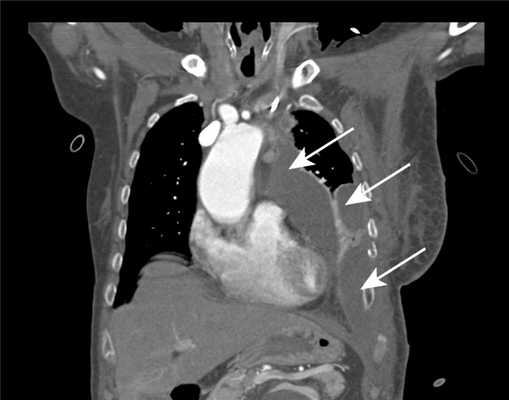

Общее состояние при поступлении средней степени тяжести. Обращали на себя внимание одышка и цианоз слизистых. По данным КТ органов грудной клетки, восходящая аорта на уровне бифуркации трахеи расширена до 4,1 см. Диаметр брахицефального ствола в области устья 1,2 см, левые общая сонная и подключичная артерии не расширены и без значимых стенозов. Диаметр дуги аорты у устья брахицефального ствола 3,6 см, в области устья левой подключичной артерии - 3,8 см, диаметр аорты в области перешейка 3,2 см. Отмечается расширение нисходящей грудной аорты от уровня перешейка до 5,9 см (ранее 4,5 см) и наличие серповидного тромба протяженностью 2,8 см в аксиальном сечении. Тромботические массы распространяются на всю грудную аорту. На уровне левого предсердия диаметр нисходящей аорты 4,5 см, у ножек диафрагмы - 3,3 см, в супраренальном сегменте брюшной аорты - 3,2 см (рис. 1). Рисунок 1. Компьютерные томограммы органов грудной клетки с внутривенным контрастированием. а - 3D-реконструкция. Расширение всей грудной аорты; б - поперечный срез. Внутрипросветный тромб, распространяющийся на нисходящую аорту.

Послеоперационный период протекал тяжело и осложнился дыхательной недостаточностью на фоне гнойного распространенного трахеобронхита. На 6-е сутки при рентгенологическом исследовании выявлено осумкованное скопление жидкости в левой плевральной полости и снижение прозрачности левого легкого (рис. 2). Рисунок 2. Компьютерная томограмма на 6-е сутки после операции. Осумкованные скопления жидкости в левой плевральной полости (указаны стрелками).